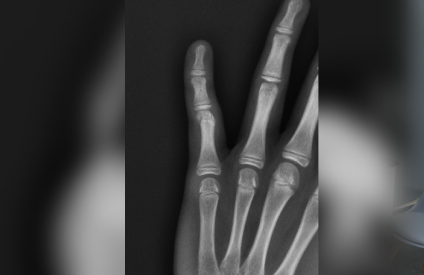

Our state-of-the-art digital X-ray facility provides immediate, high-quality imaging services right at our clinic. This advanced technology allows our specialists to quickly assess your condition and begin appropriate treatment without delay.

Digital X-rays offer superior image quality compared to traditional X-rays, with lower radiation exposure and instant availability for review, enabling faster and more accurate diagnoses.

Our digital X-ray services are essential for diagnosing various orthopaedic conditions, monitoring healing progress, and planning treatments. We use this technology for fracture detection, joint assessments, and pre-operative planning, ensuring precise and effective care for our patients.